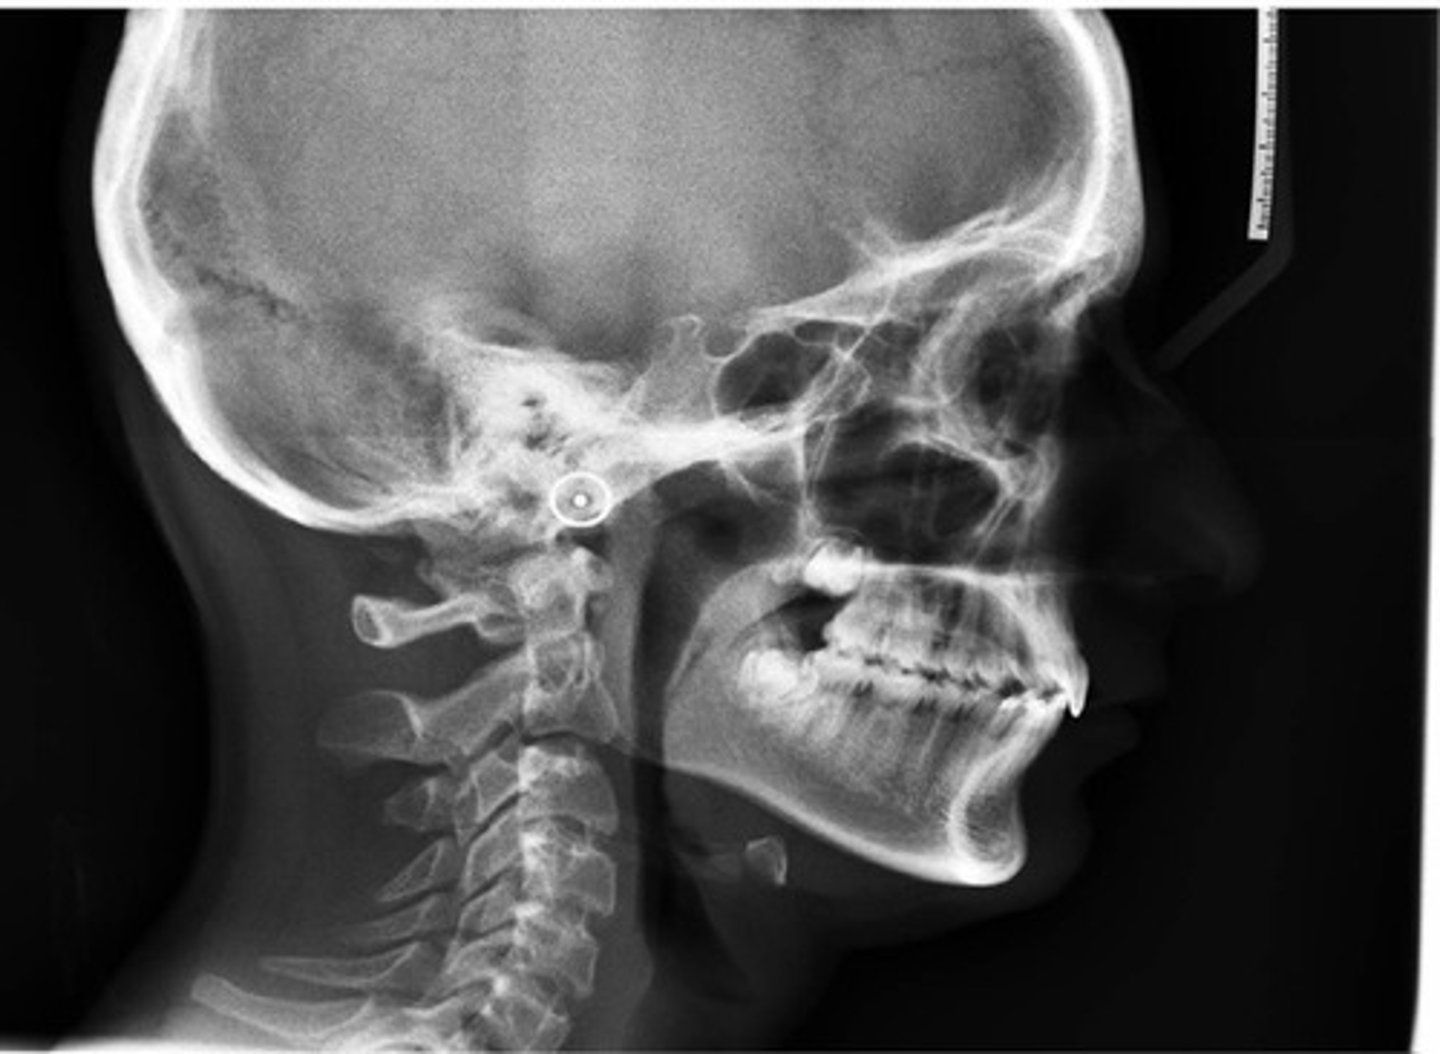

Cephalometric radiograph

extraoral radiograph of the bones & tissues of the head

Cephalometric radiograph purpose

enables the dentist to capture a complete radiographic image of the side of the face

A cephalometric radiograph is PRIMARILY used to evaluate:

lateral jaw development